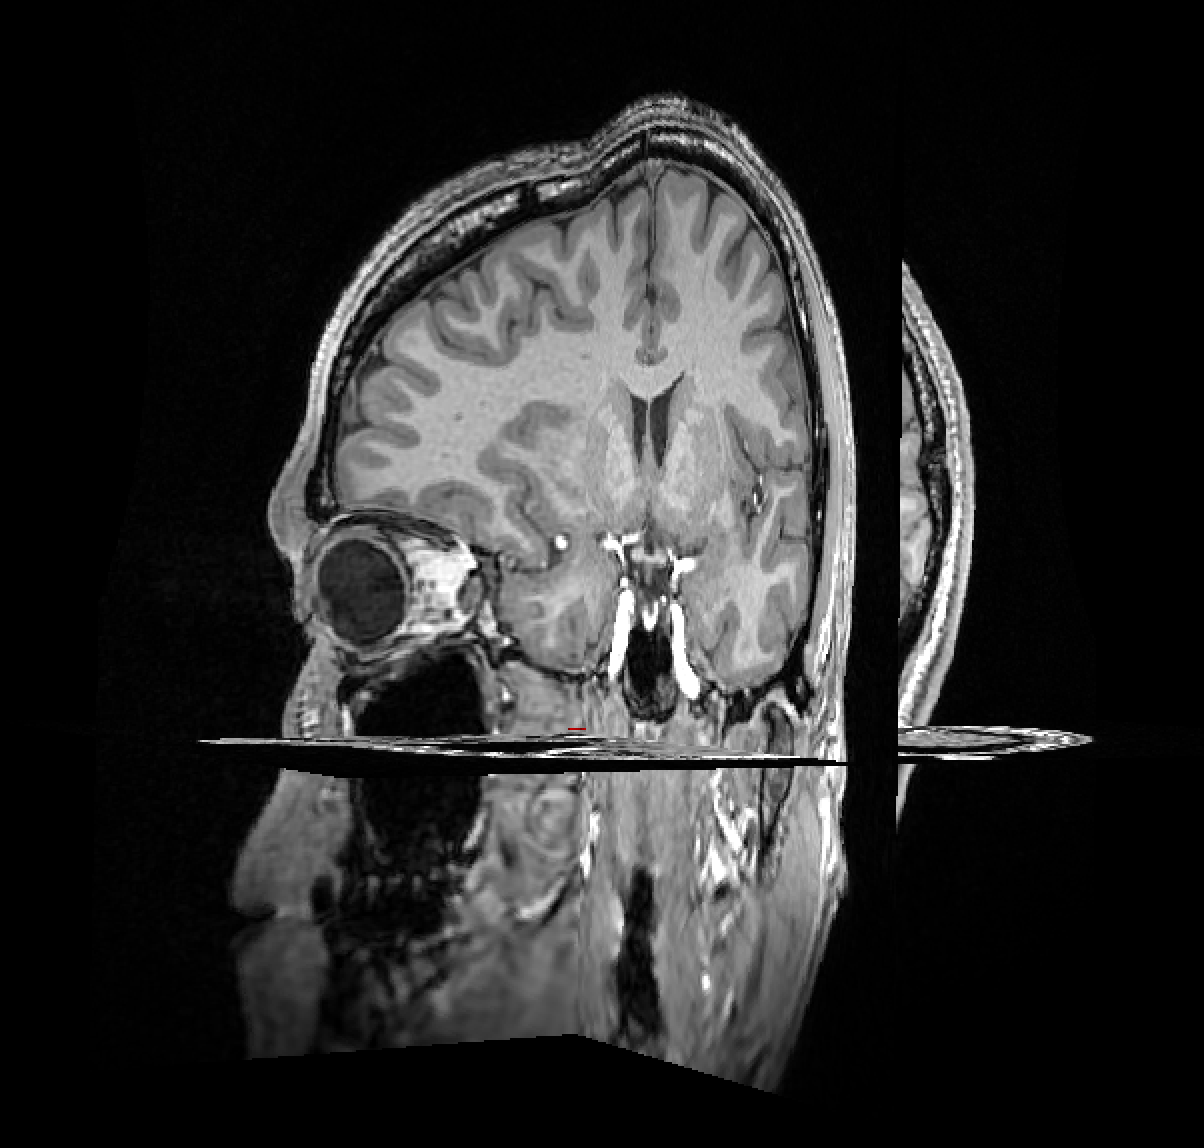

DICOM to NIfTI Conversion & FreeSurfer Segmentation

3D volumetric NIfTI file is created using dcm2niix software from DICOMs.

Automatic co-registration of multiple EEG nets during the creation of m2m folder.